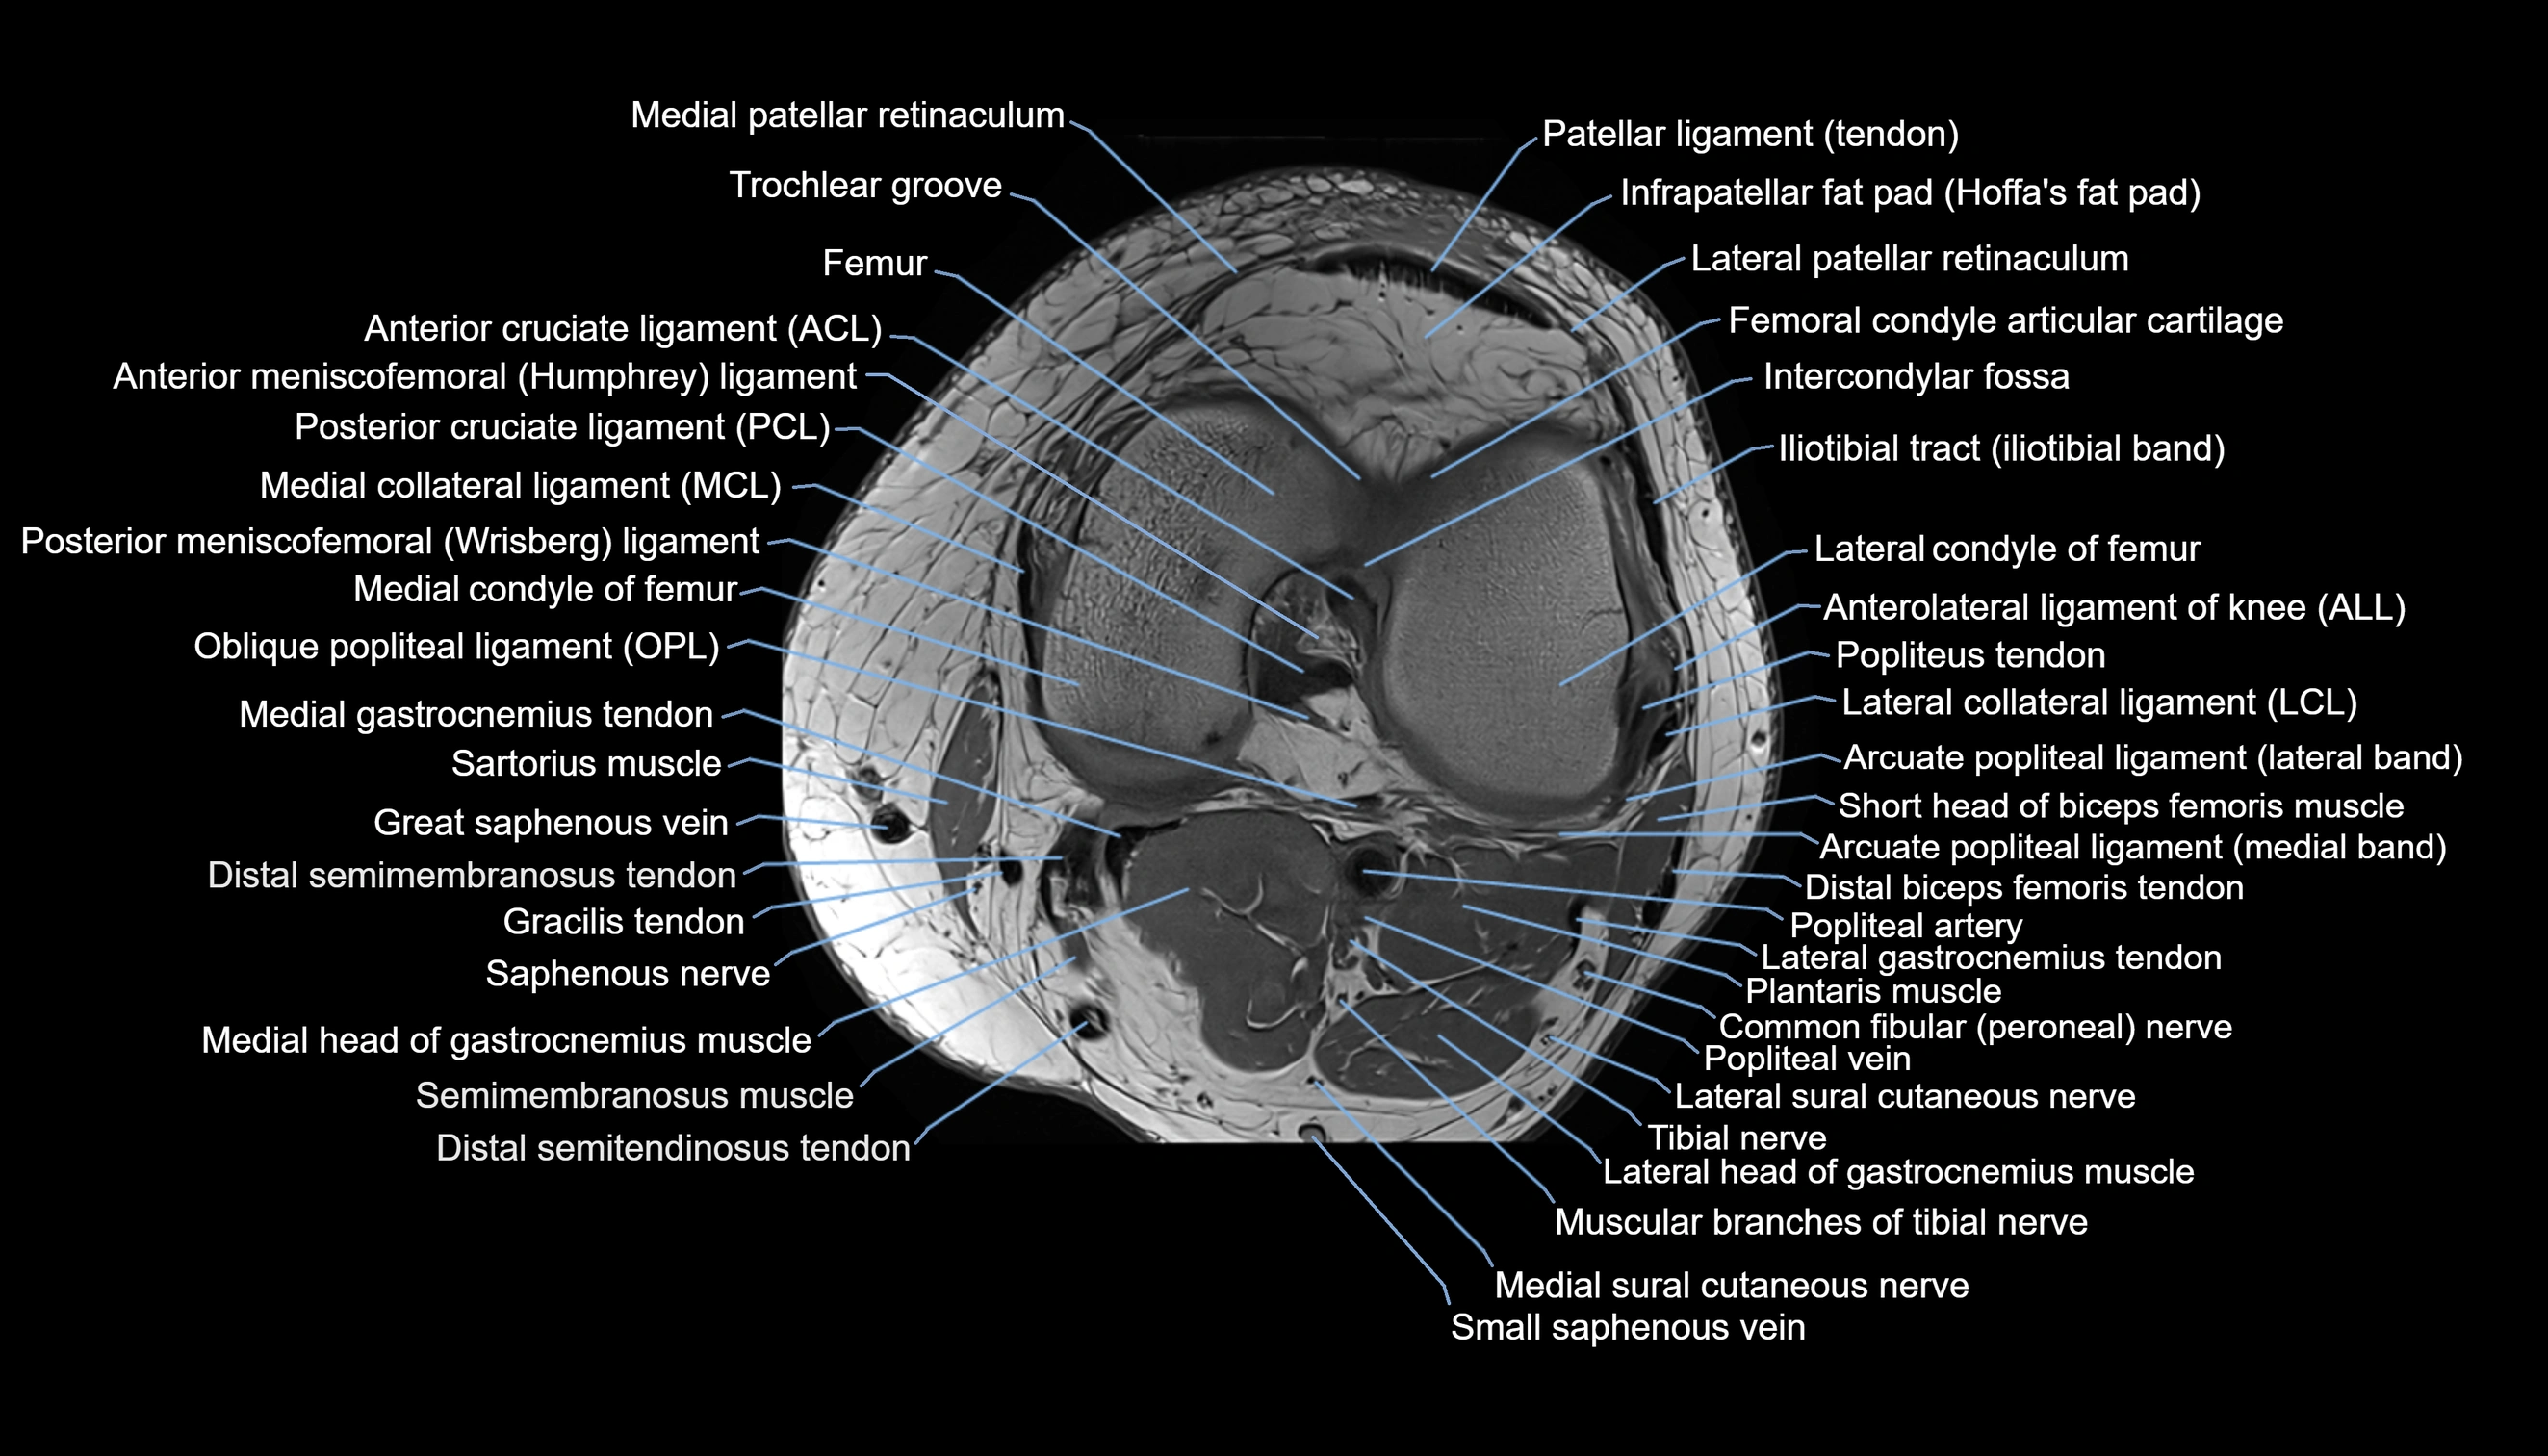

- Anterior cruciate ligament

- Anterior meniscofemoral ligament

- Anterolateral ligament of knee

- Arcuate popliteal ligament

- Femoral condyle articular cartilage

- Intercondylar fossa

- Lateral collateral ligament

- Lateral condyle of femur

- Lateral gastrocnemius tendon

- Lateral head of gastrocnemius muscle

- Lateral patellar retinaculum

- Lateral sural cutaneous nerve

- Medial collateral ligament

- Medial condyle of femur

- Medial gastrocnemius tendon

- Medial head of gastrocnemius muscle

- Medial patellar retinaculum

- Medial sural cutaneous nerve

- Muscular branches of tibial nerve

- Oblique popliteal ligament

- Patellar tendon (patellar ligament)

- Plantaris muscle

- Popliteal artery

- Popliteal vein

- Popliteus muscle

- Popliteus tendon

- Posterior cruciate ligament

- Posterior meniscofemoral ligament

- Saphenous nerve

- Sartorius muscle

- Semimembranosus muscle

- Small saphenous vein

- Trochlear groove

- great saphenous vein